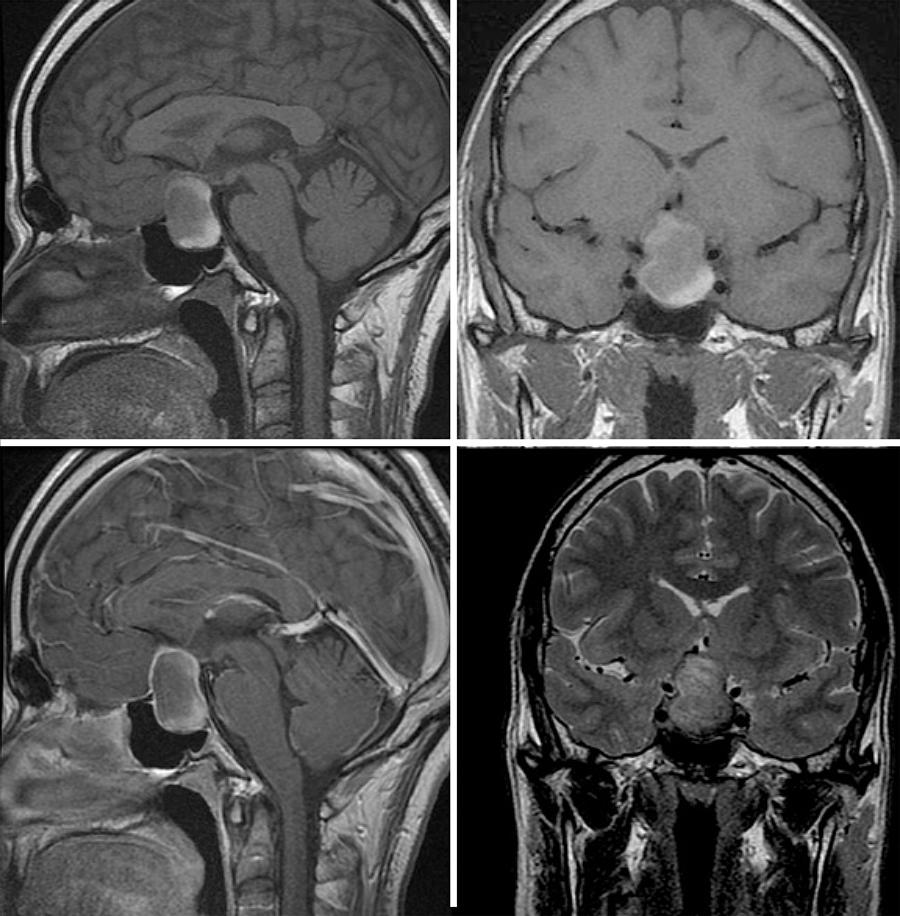

The systemic symptoms gradually resolved, but the blurred vision improved only slightly and the patient was referred for ophthalmic evaluation. His past medical history was unrevealing, except for the use of glasses for the preceding 30 years and slightly decreased vision due to anisometropic amblyopia in the right eye (OD) since childhood. On ophthalmic examination, the best-corrected visual acuity was 20/60 in OD (+3.75 sph X -0.75 cyl axis 80) and 20/300 in OS (+0.25 sph). The pupils were equal in size but a slight relative afferent pupillary defect was observed on the left side. The slit lamp findings and intraocular pressure measurements were within normal limits. Ophthalmoscopy was normal except for mild temporal optic disc pallor in OS. The visual field (VF) examination demonstrated loss of the temporal field in both eyes and constriction of the inferior nasal field in OS (Figure 1). Optical coherence tomography revealed peripapillary retinal nerve fiber layers of normal thickness in both eyes. Magnetic resonance imaging (MRI) revealed a tumor in the sellar region with extension to the suprasellar cistern and compressing the optic chiasm. Heterogeneous areas in the tumor suggested intralesional bleeding. The lesion showed a hyperintense signal on T1-weighted images and a hypointense signal on T2-weighted images, indicating hemorrhage inside the cystic tumor (Figure 2). Subsequently, the patient developed nausea and vomiting. A repeat laboratory investigation revealed a marked decrease in cortical and adrenocorticotrophin (ACTH) hormone levels, indicating adrenal insufficiency. The patient was submitted to urgent transsphenoidal surgery. The histological characteristics of the tumor were consistent with RCC (Figure 3).

Figure 2 Magnetic resonance imaging scan showing a cystic sellar and suprasellar tumor with chiasmal compression. There were areas of hyperintense signal on T1-weighted images on sagittal (upper left) and coronal (upper right) sections. The lesion has a similar appearance on contrasted T1-weighted image, after gadolinium injection (lower left) and shows hypointense signal on coronal T2-weighted image (lower right). Observe that the hyperintense (on T1) and hypointense (on T2) areas are present in the lower and posterior part of the lesion, compatible with hemorrhage.